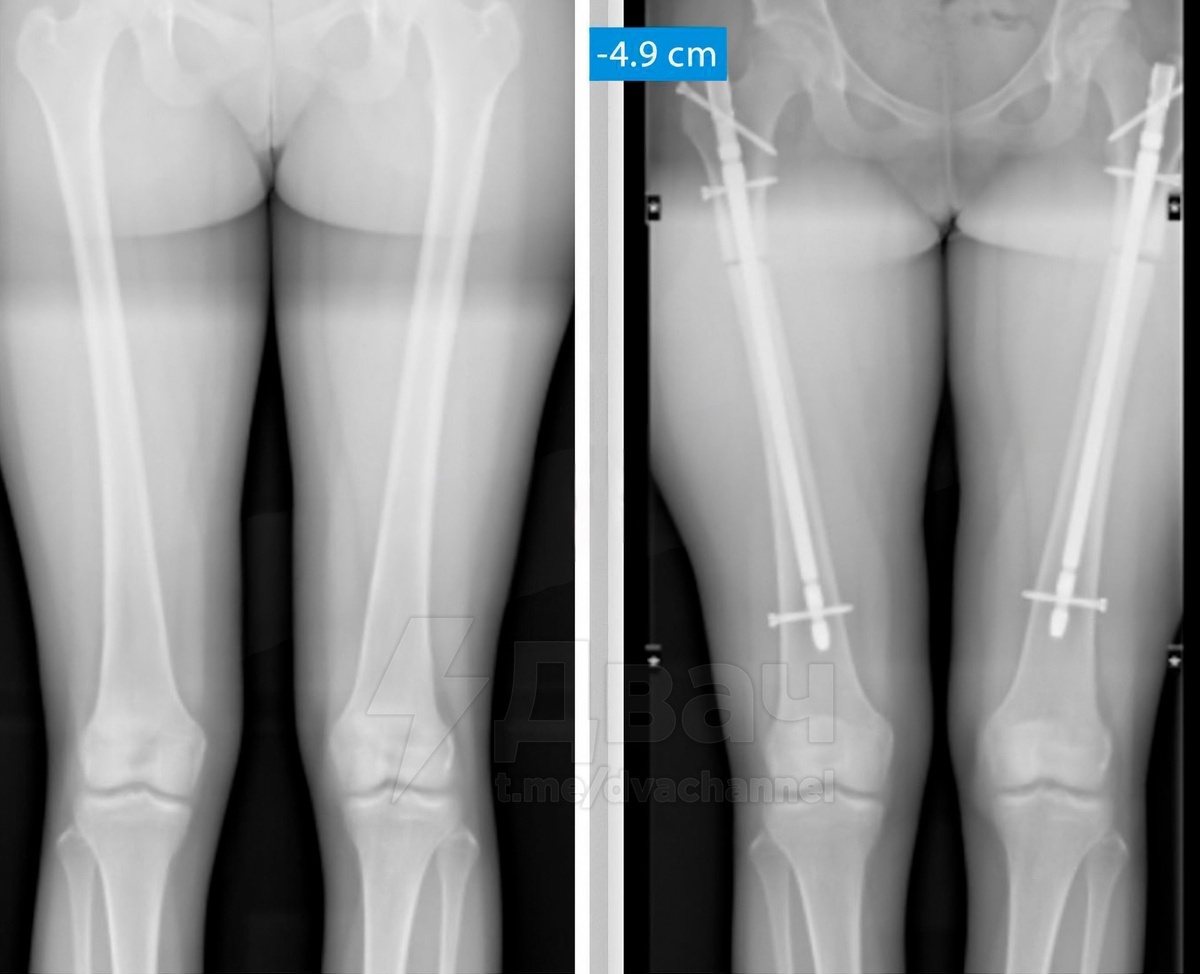

Девушки сутулятся, чтобы казаться ниже, отказываются от каблуков, некоторые девушки даже идут на операции по укорачиванию ног, чтобы стать ниже ростом. Они, видимо, совсем сошли с ума: как можно отказываться от такой красоты? Вот к чему приводят подобные комплексы.